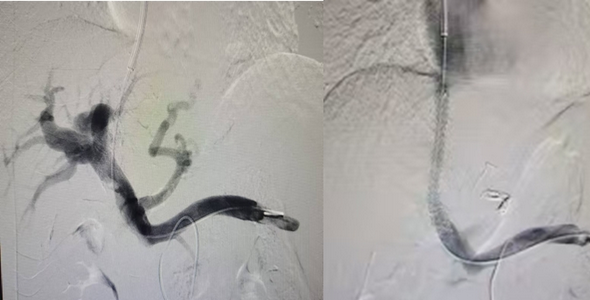

术前、术后造影对比图

此次手术从颈静脉进入肝静脉,从肝静脉穿刺门静脉,利用支架建立血流通路,使门脉血直接从肝静脉回流至心脏,从而达到降低门脉高压后控制和预防食管胃底静脉曲张破裂出血、促进腹水吸收的目的,手术顺利,目前患者恢复良好。